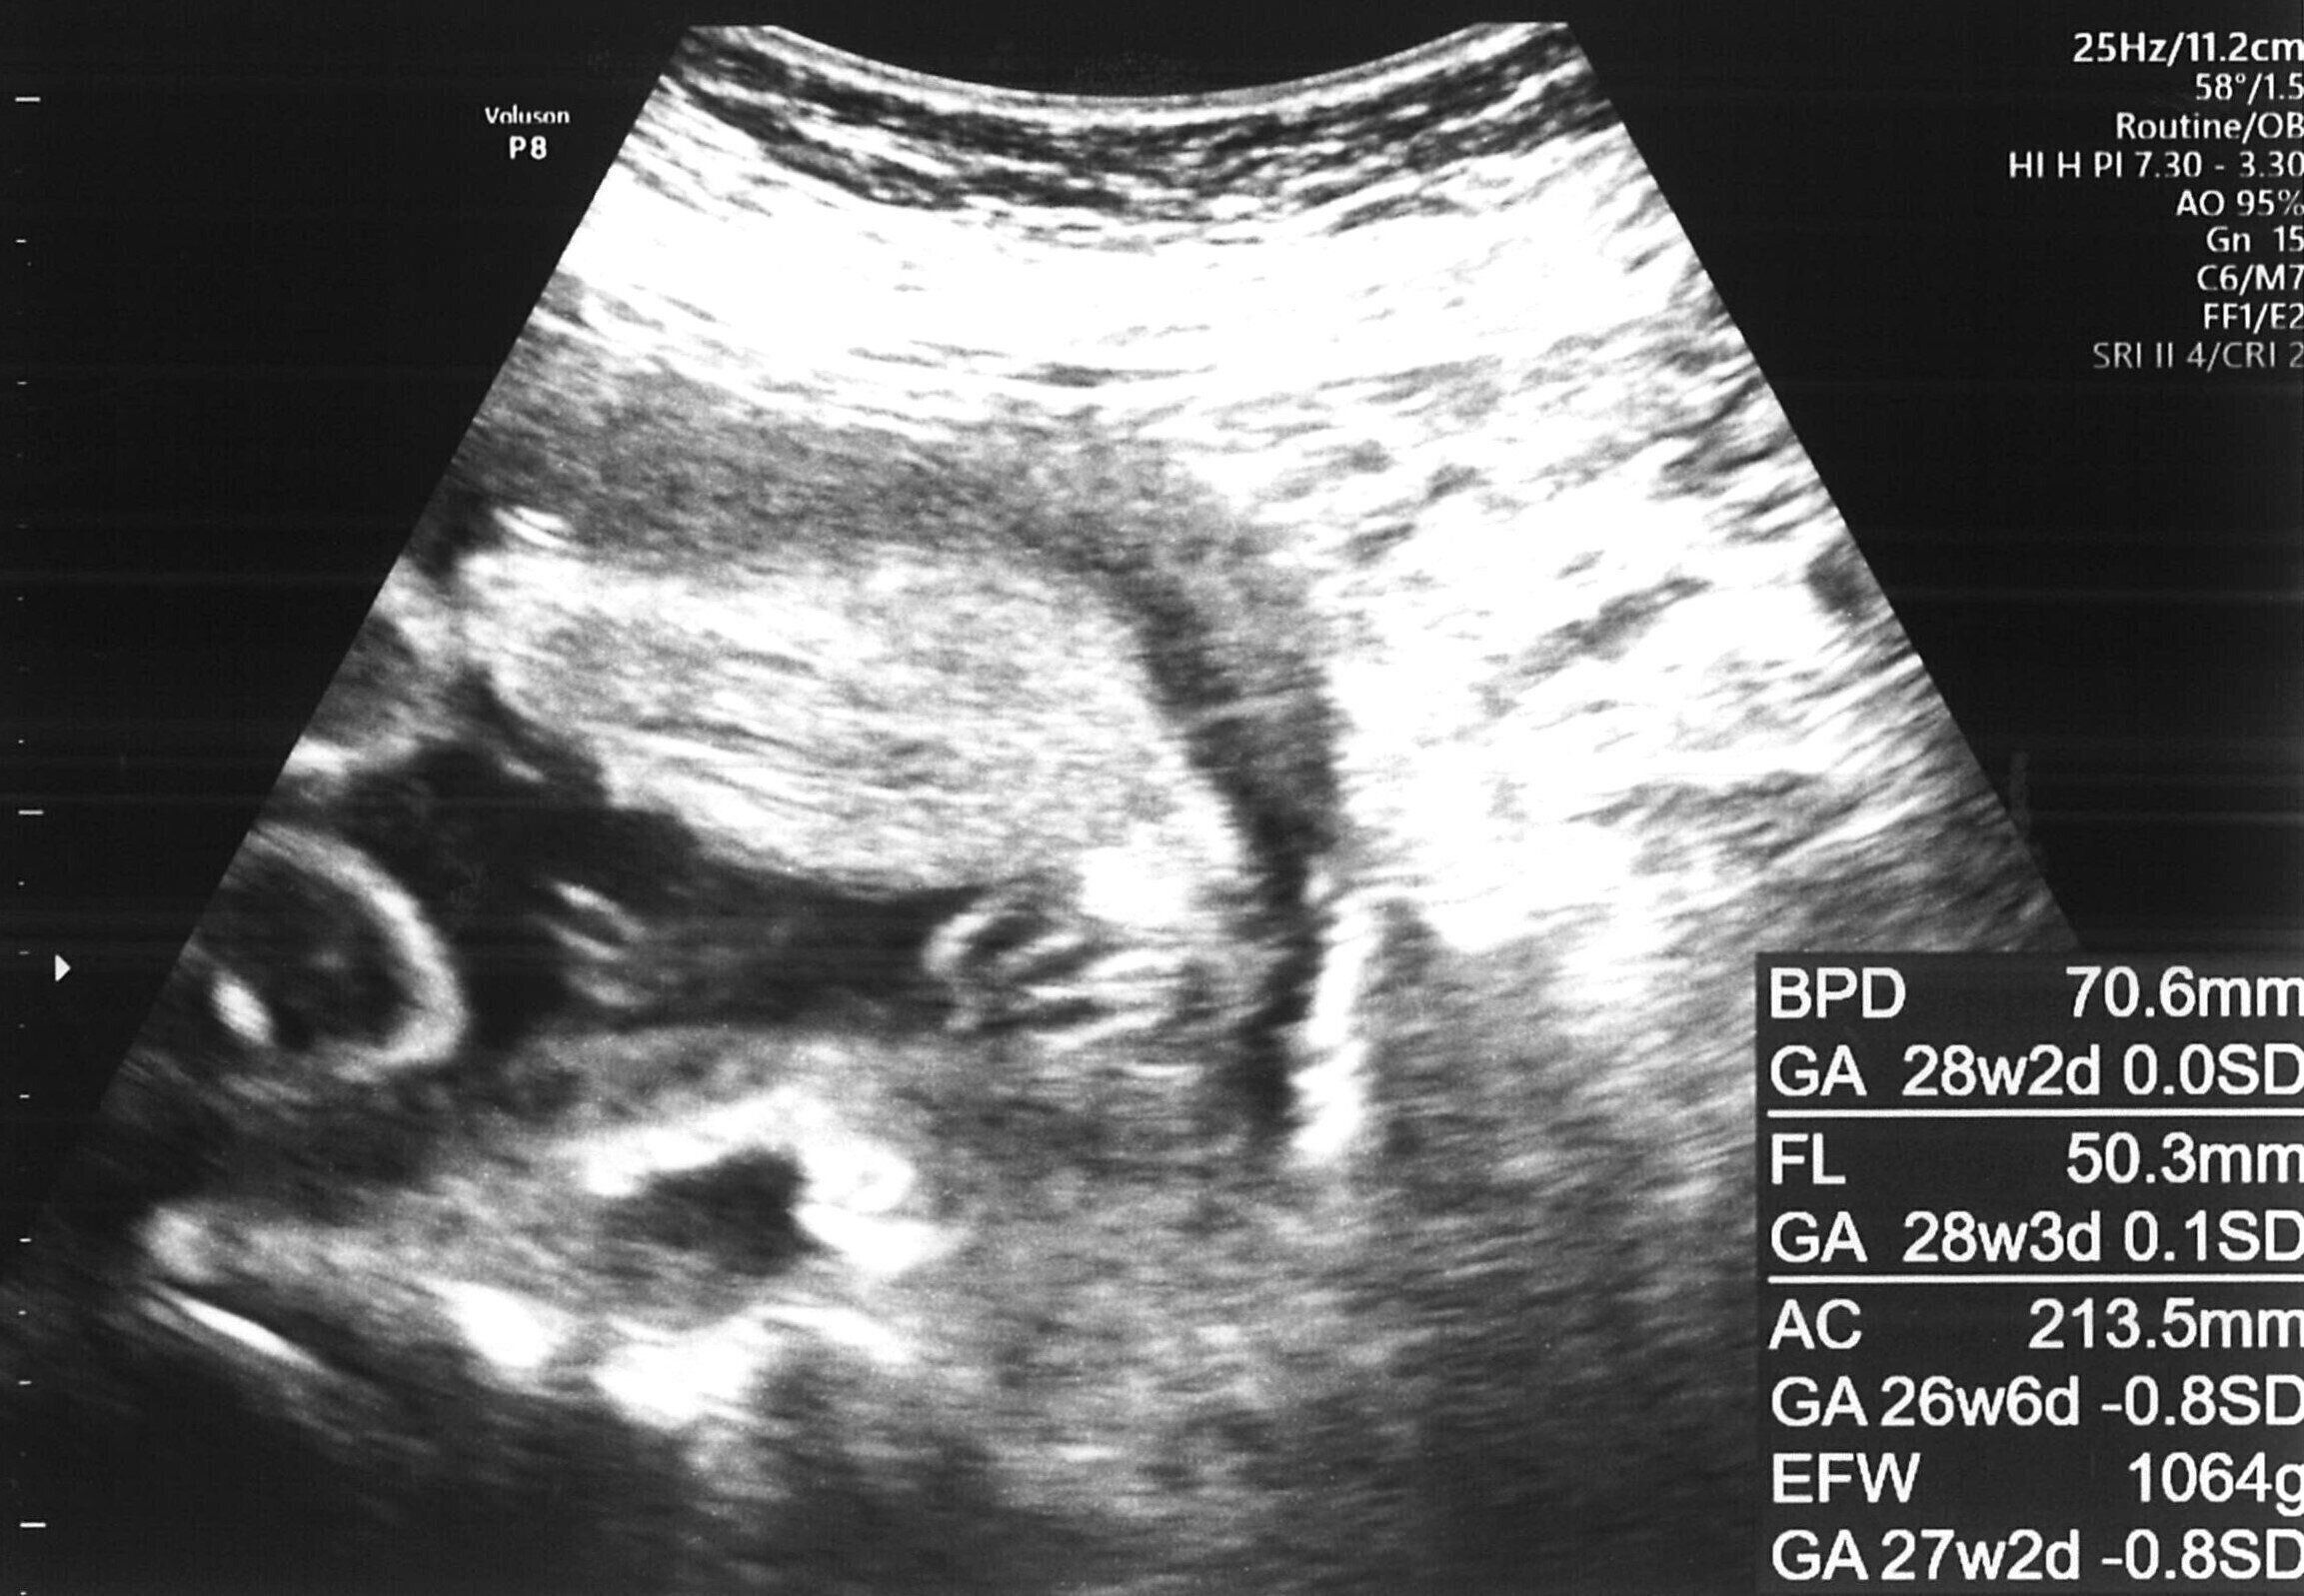

でもその後、いろいろと話をしていく中で、彼とは人生のスタンスが違うと感じ、お別れすることにしました。2024年12月に第1子を出産する予定ですが、シングルマザーとして育てていきます。